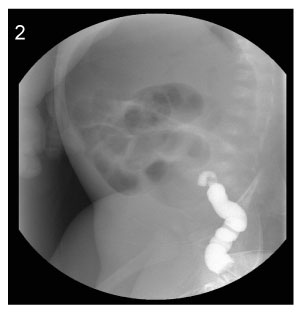

Fig. 1

Image of simple X-ray at the age of 8days (Case No. 3).

Fig. 1 Image of simple X-ray at the age of 8days (Case No. 3).